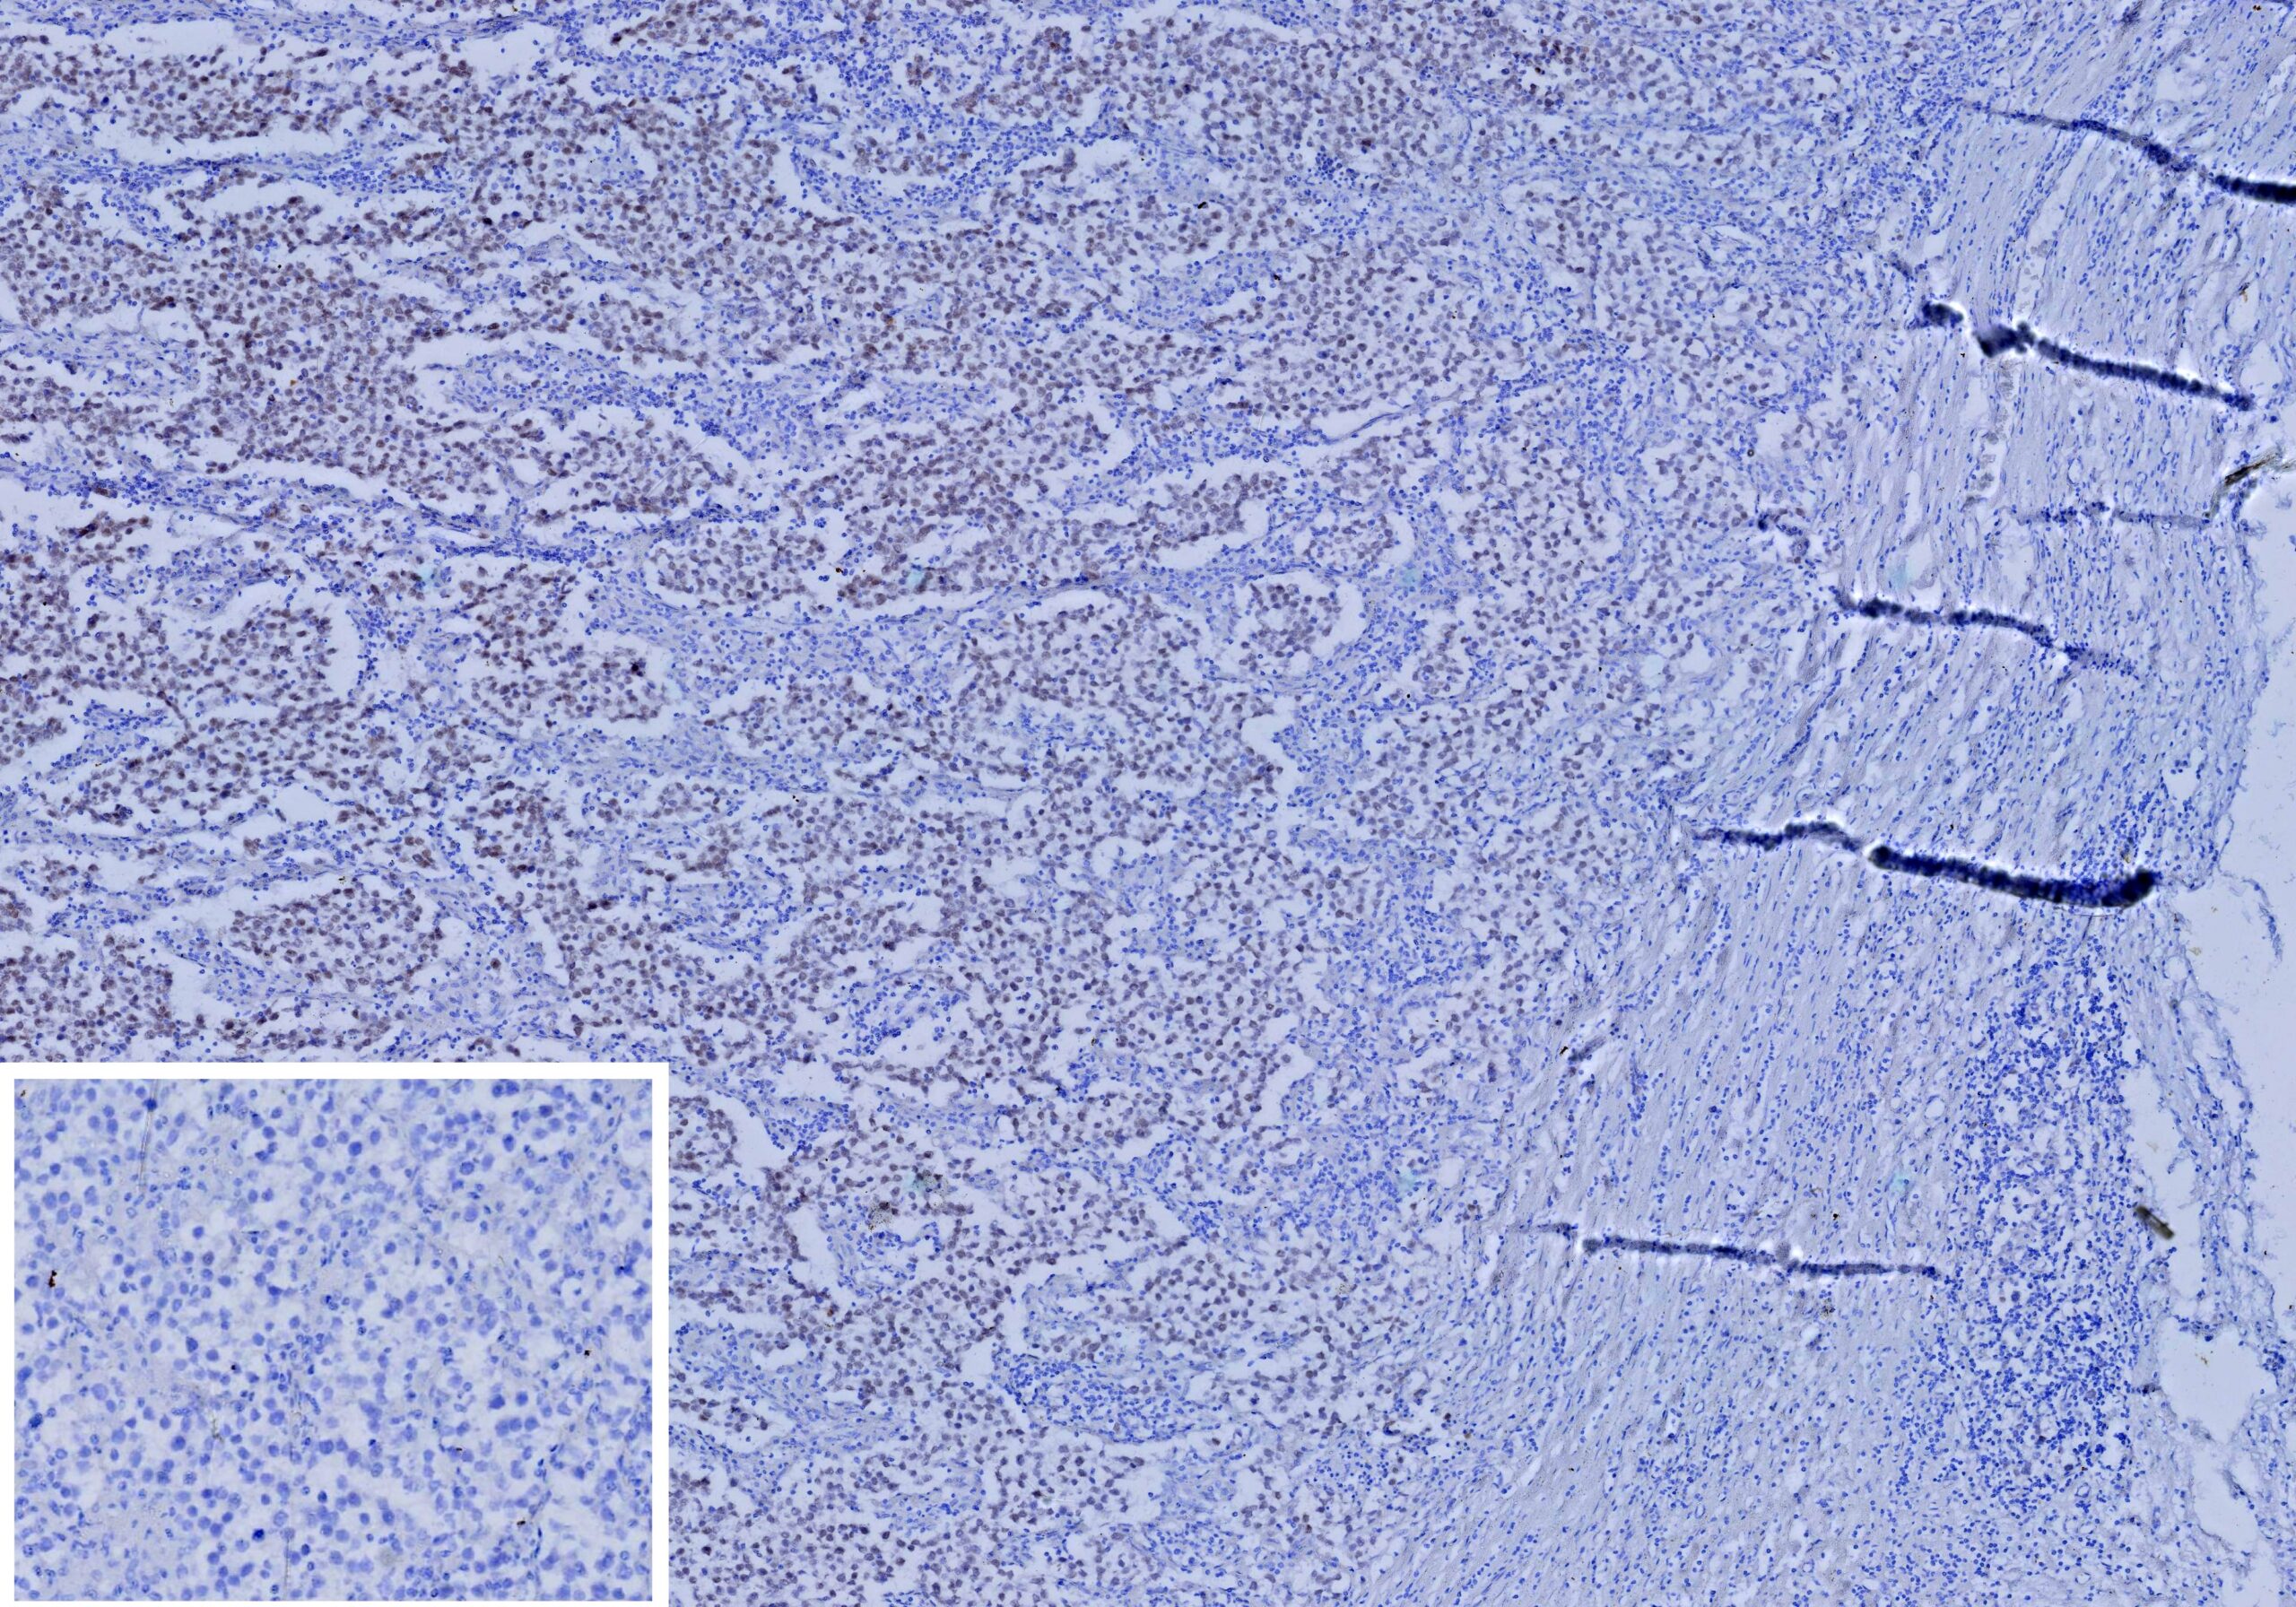

Formalin-fixed, paraffin-embedded human seminoma stained with SALL4 Recombinant Rabbit Monoclonal Antibody (SALL4/13721R). HIER: Tris/EDTA, pH9.0, 45min. 2°: HRP-polymer, 30min. DAB, 5min. Inset: PBS instead of primary antibody; secondary only negative control.